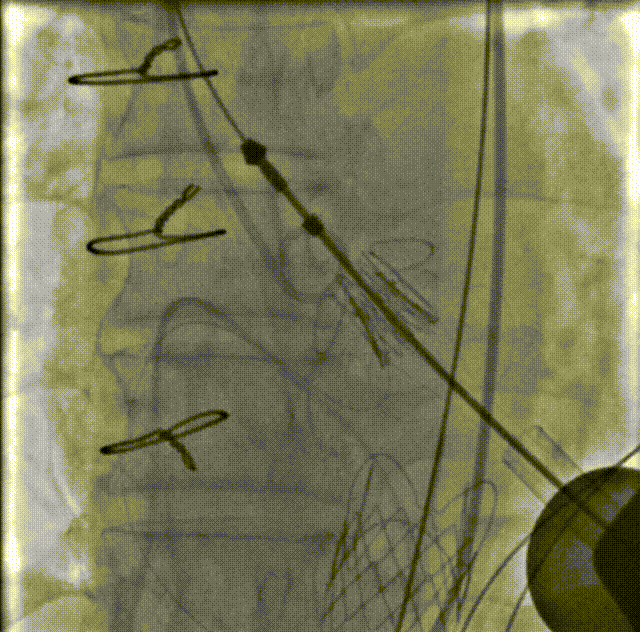

术前造影

瓣膜仓入位

瓣膜仓打开

锁丝释放

第一个主动脉瓣锁丝释放后,瓣膜脱落进入主动脉。球囊拖瓣膜至降主动脉

二次瓣膜仓入位

瓣膜打开

球囊后扩

二尖瓣入位

主瓣造影

左室造影